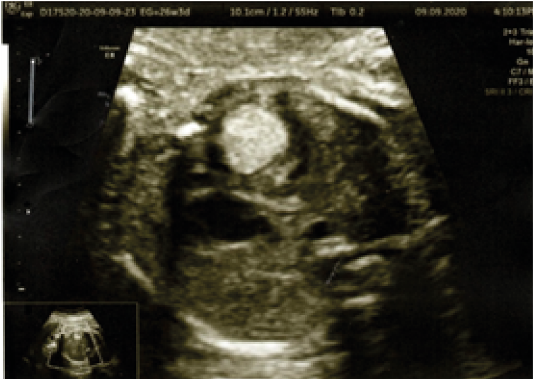

Los rabdomiomas son tumores cardiacos fetales raros que pueden estar presentes hasta un 86 %. Se encuentran mayormente en el tabique interventricular, pared libre de aurícula o ventrículo y poco frecuente en las válvulas auriculoventriculares. Depende del tamaño del tumor para tener repercusión hemodinámica fetal.

Al examen ecográfico se observa lesión hiperecogénica en el tabique interventricular con protrusión a la cavidad ventricular derecha, acompañado de desviación leve del tabique interventricular y asociado al momento del examen con arritmia de tipo ventricular.